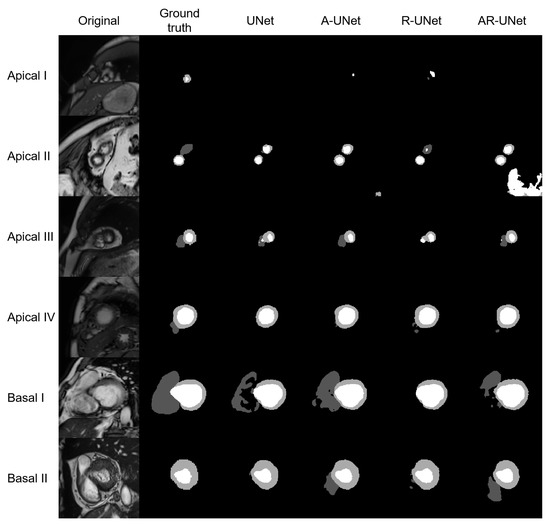

The model performance of four S-UNets is shown in Table 4. From both slice-level and subject-level evaluations, the A-UNet showed the highest 2D and 3D scores within all anatomical structures (2D DSC: 0.863 for RVC, 0.872 for MYO and 0.940 for LVC; 3D DSC: 0.928 for RVC, 0.886 for MYO, and 0.962 for LVC). However, the detection of low-quality segmentations is more important in a QC system. Therefore, we visually inspected the testing segmentations and noticed that low-quality segmentations was mainly distributed at the apical or basal levels. Figure 3 shows six examples of low-quality segmentations.

Figure 3. Shows six examples of low-quality segmentations, including four apical slices and two basal slices. From left to right, the original images, manually derived masks and automatic segmentations for the four S-Unets are listed, respectively. The I to IV shows that images were derived from different subjects.

As shown in Table 4, our DSC scores for 2D segmentations were 0.863, 0.940, and 0.872 for RVC, LVC, and MYO, respectively. These results demonstrate that our model structure is suitable for the segmentation task. However, as depicted in Figure 3, our four S-Unets exhibited a decreased segmentation performance on certain apical and basal slices. This phenomenon was also observed in the recent SAM segmentations (Figure 10). During our analysis, we observed that S-Unets with various modifications (residual, attention parts) exhibited slightly varying performances on ambiguous regions of interest (ROIs). For instance, S-Unets equipped with attention structures tended to segment the right ventricular cavity more accurately in basal slices, while those with residual parts displayed better performance levels on smaller ROIs (Figure 3). Moreover, the variability of low-quality segmentations offered unique samples for our radiomics dataset. This variability partially explains why we incorporated modified model structures in our analysis pipeline.